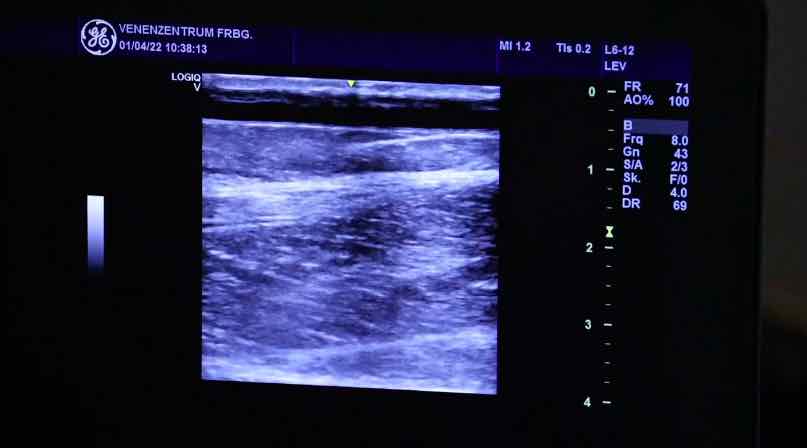

15. Freiburger Venen-Workshop – thumbnail 1 of 8 15. Freiburger Venen-Workshop – thumbnail 2 of 8 15. Freiburger Venen-Workshop – thumbnail 3 of 8 15. Freiburger Venen-Workshop – thumbnail 4 of 8 15. Freiburger Venen-Workshop – thumbnail 5 of 8 15. Freiburger Venen-Workshop – thumbnail 6 of 8 15. Freiburger Venen-Workshop – thumbnail 7 of 8 15. Freiburger Venen-Workshop – thumbnail 8 of 8

15. Freiburger Venen-Workshop

Live-Operationen - Endovenöse Technik sinnvoll einsetzen